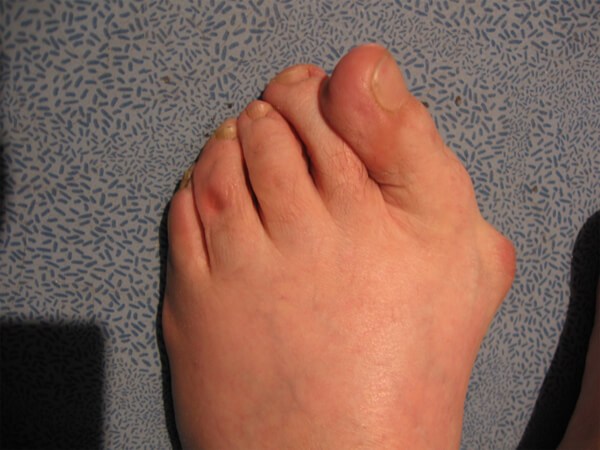

하이힐을 즐겨 신는 여성들의 발을 보면 엄지발가락과 새끼발가락이 서로 안쪽으로 휘어져 있는 것을 볼 수 있다. 좀 더 정확히 얘기하자면 엄지발가락의 제1중족 발가락 관절을 기준으로 발가락 쪽의 뼈가 바깥쪽으로 치우치고, 발뒤꿈치 쪽의 뼈는 반대로 안쪽으로 치우치는 발 변형을 말하는데, 이를 무지외반증이라고 한다.

무지외반증의 가장 흔한 증상은 제1중족 발가락 관절 안쪽의 돌출 부위의 통증이다. 무지외반증으로 변형된 발가락 부위가 신발에 자극을 받아 두꺼워지고 염증이 생겨 통증까지 발생한다. 2차적으로는 두 번째 또는 세 번째 발가락의 발바닥 쪽에 굳은살이 생기고 통증이 발생하기도 하며, 심한 경우에는 두 번째 발가락이 엄지발가락과 겹쳐지거나 관절이 탈구되기도 한다.

일단 무지외반증이 있는 발은 외형적 변형만으로 진단할 수 있다. 하지만 적절한 진단과 치료를 위해서는 의사의 진단이 필요하며(통증이 심한 경우에는 필수) 정도에 따라서는 진찰뿐만 아니라 방사선 촬영 검사가 필요하기도 하다.